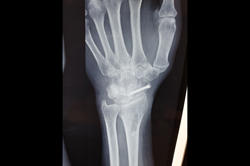

Scaphoid